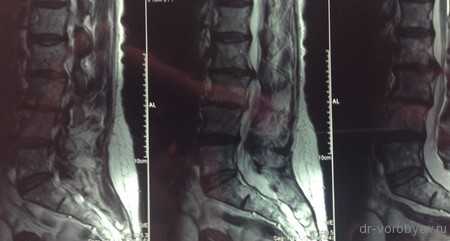

МРТ до операции